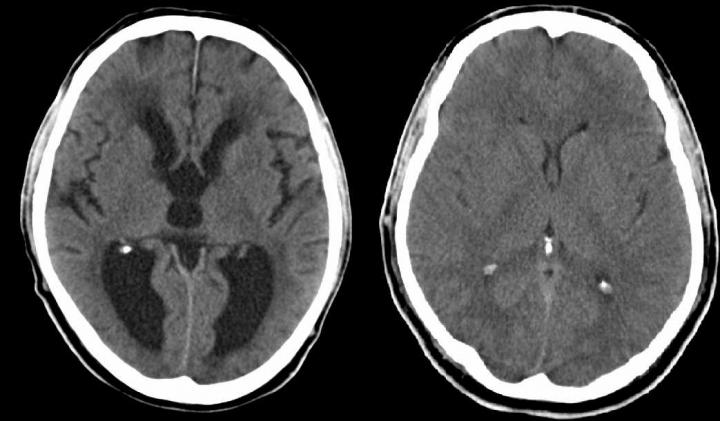

CT of Patient with Hydrocephalus (IMAGE) Sanford Burnham Prebys Caption This is a CT of a patient with hydrocephalus. Credit MBq via Wikimedia Commons Usage Restrictions None License Licensed content Disclaimer: AAAS and EurekAlert! are not responsible for the accuracy of news releases posted to EurekAlert! by contributing institutions or for the use of any information through the EurekAlert system.